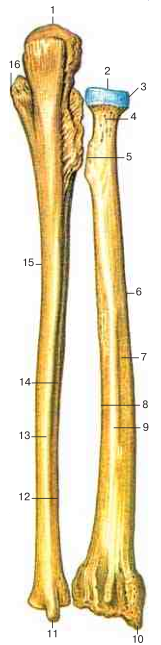

Радиоульнарный угол: строение и особенности лучевой кости